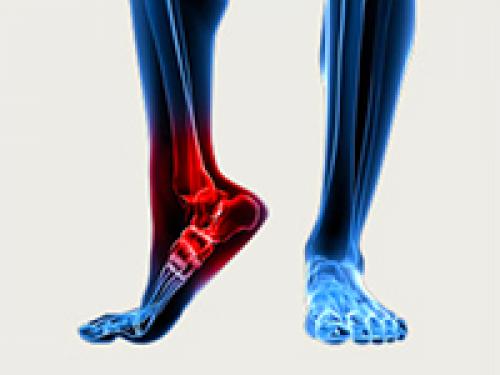

Артроз стопы. Лечение артроза стопы

Резкая боль в стопе, деформация пальцев, появление болезненных мозолей, изменение походки, быстрая утомляемость и даже инвалидность – все это может стать реальностью, если вовремя не выявить и не начать лечить артроз стопы, или остеоартроз. Это хроническое заболевание, симптомы которого на начальных стадиях пациенты просто игнорируют, не придавая им особого значения. А суставы в это время незаметно, но постепенно, разрушаются.

Подобные изменения сопровождаются нарушениями обмена веществ в хрящевых тканях и микроциркуляции крови, а также возникновением воспалительного процесса. Причем артроз может возникнуть не только у людей в возрасте, но и у молодых мужчин и женщин, которые активно занимаются спортом.

Любая локализация артроза имеет серьезные осложнения, поэтому не стоит затягивать с лечением.

Причины артроза стопы

Существует множество факторов, которые могут спровоцировать возникновение этого заболевания. К тому же, не всегда оно протекает самостоятельно, а является следствием других нарушений. Однако врачи выделяют основные причины артроза стопы, описанные ниже:

- Врожденные или приобретенные патологии стопы, например плоскостопие, деформированные суставы или пальцы, дегенеративные изменения и т.д.

- Большие нагрузки на область подвижных суставов при длительной ходьбе или переносе больших грузов, вызывающие сначала отек, а затем и сам артроз.

- Разнообразные травмы и ушибы у спортсменов, а также избыточная масса тела у людей, страдающих ожирением.

- Переохлаждение, нарушение обменных процессов, наличие эндокринных заболеваний, неудобная обувь, неправильный образ жизни, высокий рост и т.д.

Симптомы артроза стопы

Как правило, разные пациенты могут иметь разную симптоматику. Она зависит как от стадии развития болезни, так и от ритма жизни человека. Более того, симптомы артроза стопы схожи с симптомами артрита. Однако важно помнить, что от правильно поставленного диагноза зависит и успех лечения:

- Тупая боль в суставах при длительной ходьбе, тугоподвижность, а также грубый хруст, который провоцируют неровности поверхности суставов.

- Деформация стопы, покраснения кожи в пораженной области, отечность и припухлость, вследствие чего возникает нарушение походки.

- Высокая утомляемость, снижение работоспособности и возникновение мозолей в области пораженных суставов.

- Появление костных разрастаний, которые в будущем могут прорваться наружу, а также нарушение функции суставов, которые возможны на поздних стадиях болезни.